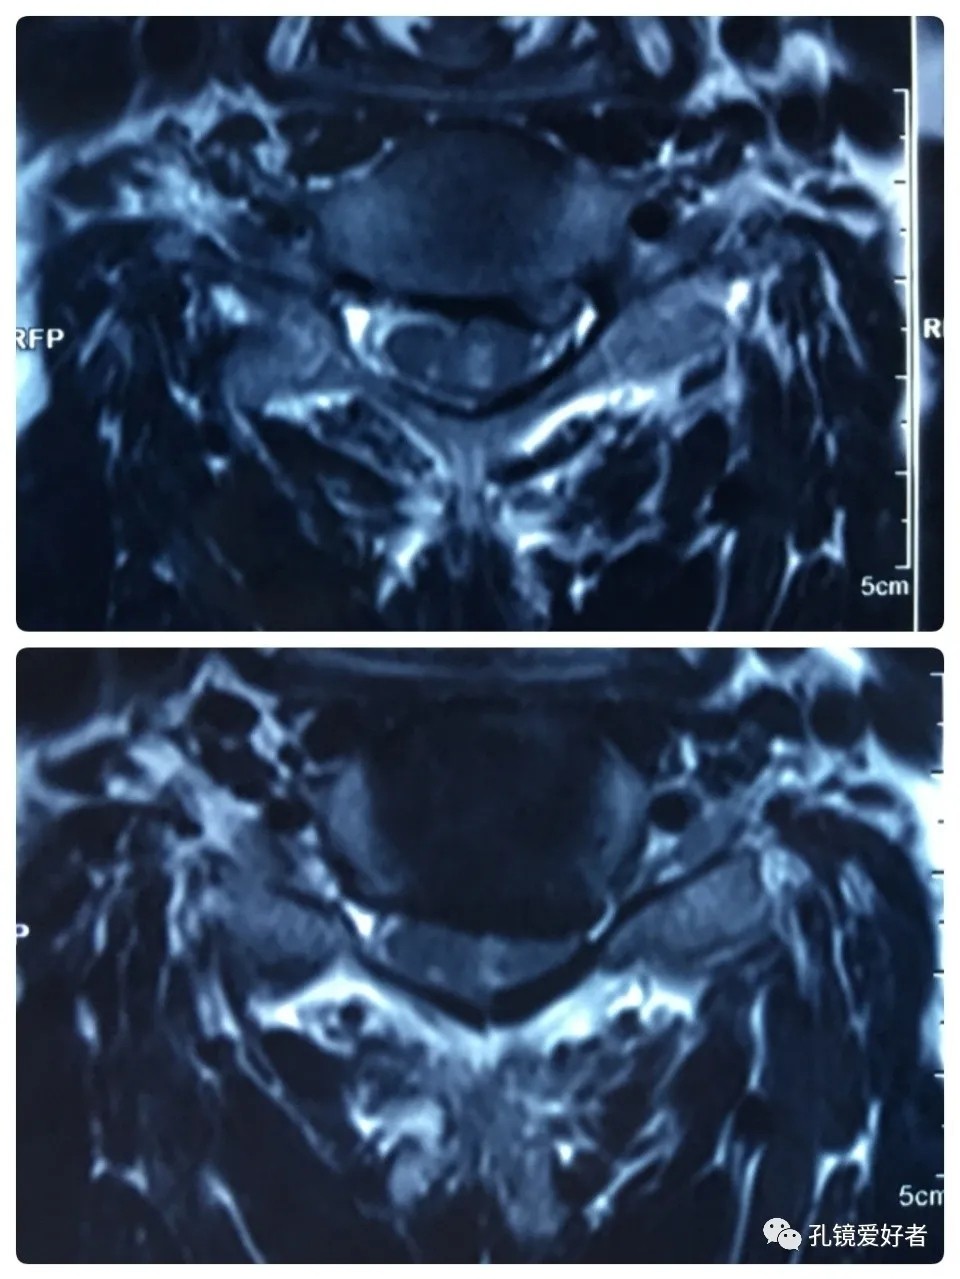

The patient's preoperative imaging data

Then let's look at MRI.

The MRI shows that the cervical stenosis is on C3-4, C5-6 and C6-7. Considering the patient's clinical symptoms, C5-6 and C6-7 are the main affected segments. So it’s advised that the patient undergo posterior cervical open-door laminoplasty. According to the patient, he had visited many hospitals before and received similar proposals of diagnosis and treatment- posterior cervical open-door laminoplasty. The reason he came to our hospital was that he wanted his surgery could be performed in a minimally invasive way. After considerable preoperative discussion with my colleagues and the patient, we decided to perform the minimally invasive endoscopic decompression for C5-6 and C6-7 double-segment stenosis through posterior approach (with the Delta system).